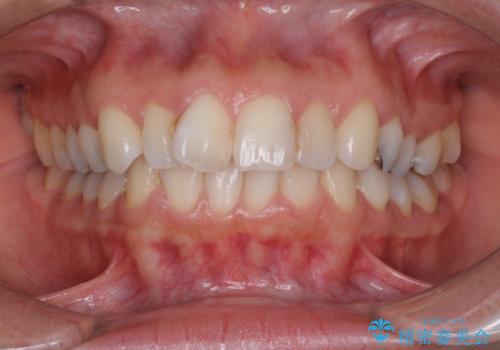

- 上の前歯の捻じれと突出感を気にして来院された患者様です。

目立たない装置を希望とのことで、上顎左右第一小臼歯を抜歯し、インビザラインにて矯正治療を行うこととしました。